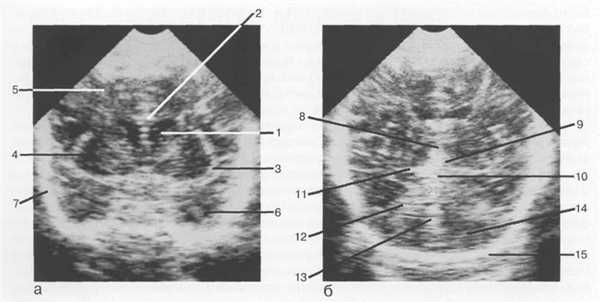

Рис. 1.2. Нейросонография. Изображения головного мозга в корональной плоскости: а — через передние рога боковых желудочков; б — через структуры задней черепной ямки.

1 — передний рог бокового желудочка; 2 — мозолистое тело; 3 — латеральная щель мозга; 4 — островок; 5 — лобная доля; 6 — височная доля; 7 — чешуя височной кости; 8 — III желудочек; 9 — цистерна промежуточного паруса; 10 — четверохолмная цистерна; 11 — охватывающая цистерна; 12 — намет мозжечка; 13 — червь мозжечка; 14 — полушария мозжечка; 15 — затылочная кость.